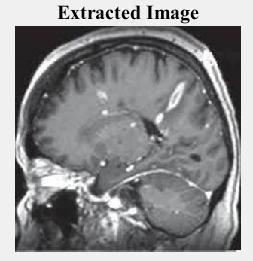

Fig -5(e): Decryptedandextractedimage

The decrypted image is generated by applying the decryptiontothecompressedimage,asshowninfig.5(e).The extractedwatermarkedimageispresentedontheright.By applying the De-watermarking, the Brain MRI image was retrievedfromthewatermarkedimage.